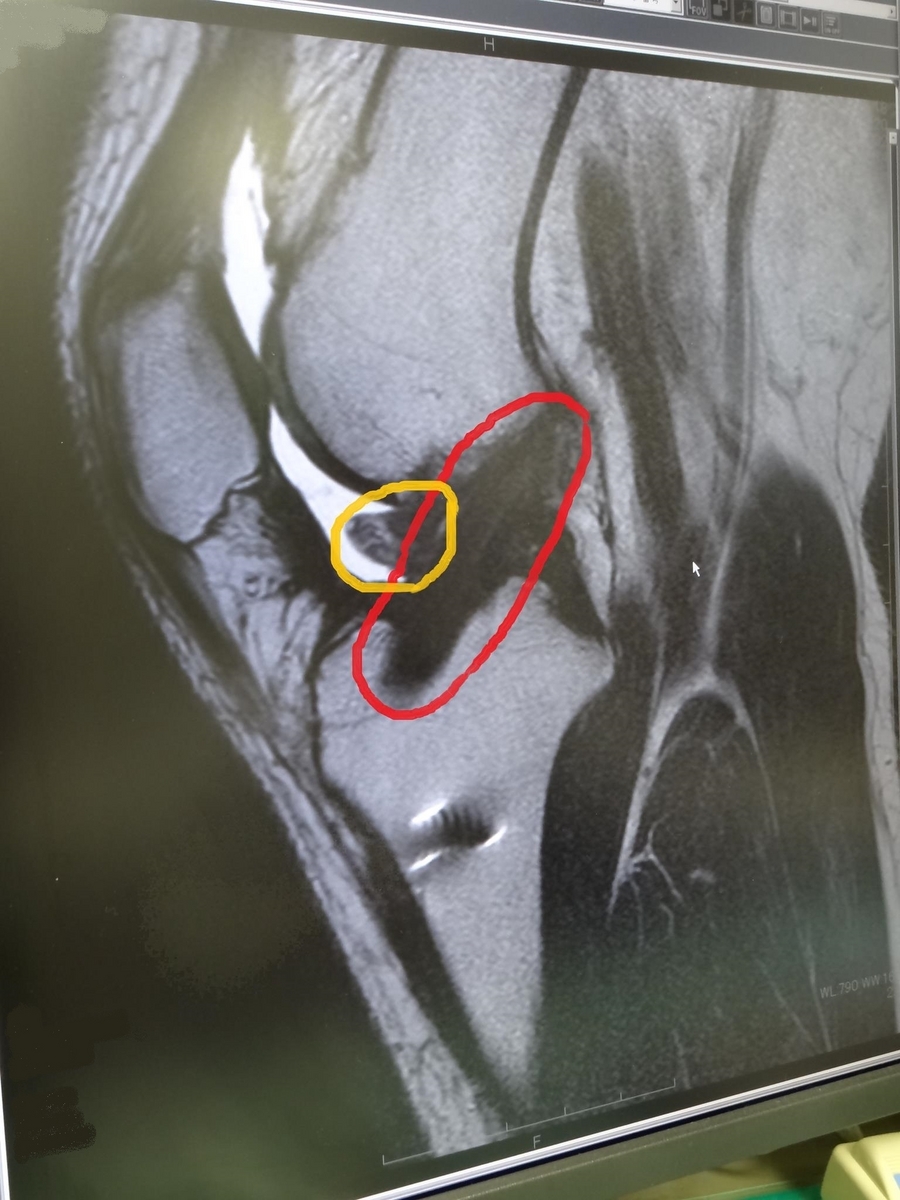

2013-04-18 通院やらいろいろ 右膝 右膝前十字靭帯(ACL)再建 買い物 参詣 自転車 EscapeAIR号 髪の毛 赤い斜めな黒いのが再建された前十字靭帯。 黄色いのが余計に成長した靭帯(過成長)で伸ばすのに邪魔してるかも?とのこと。 素人目?に「しっかりした靭帯出来てんじゃね?」と勝手に思ってみたり。 それから財布の修理&長財布の発注。 瑞雲寺の小早川秀秋公のお墓へ(お墓は本堂の中)。 整体に行ってから、お世話になってる自転車屋さんでメンテナンス。 散髪して帰宅。